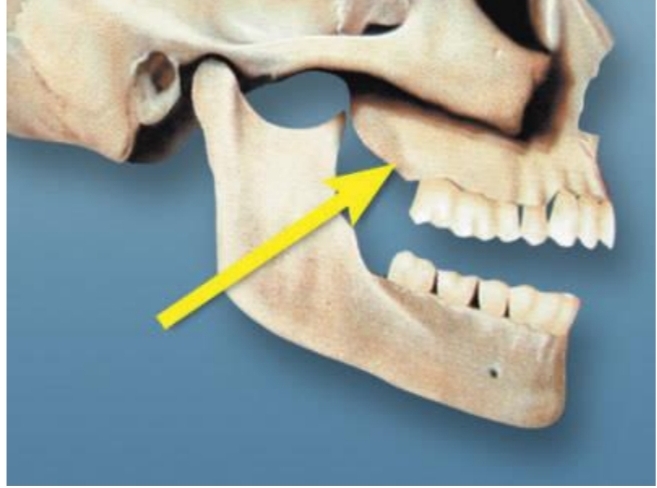

Opening in bone (slight depression)

Located bilaterally between eye (orbit) and canine/premolar root area

Infraorbital nerve infiltrates with anesthetic for maxillary anterior teeth

Infraorbital Foramen